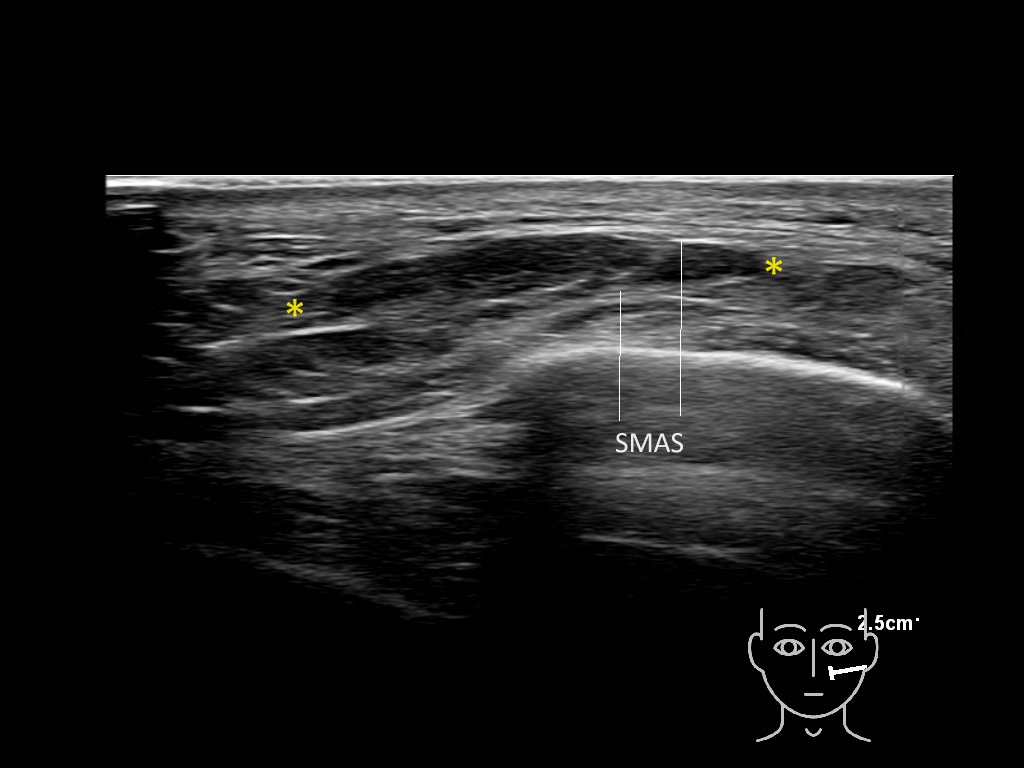

Filler deposits may end up unintentionally in the SMAS or fascial layers of the skin. Very often this will not lead to adverse events, however, adverse events ( nodules, migration / redistribution impaired muscle movement and smiling and malar edema) are are often related to filler ending up in the SMAS or fascia.

Study the first image to recognize the different layers. If you are sure about the layers, swipe to the second image to view the answer (if applicable).